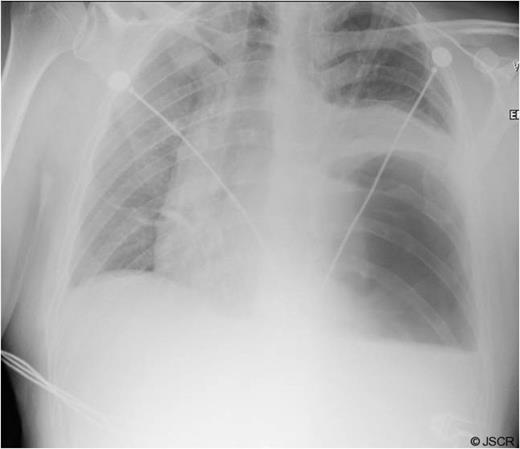

During the sac dissection, the patient developed tension pneumothorax due to an iatrogenic tear of the right pleura requiring a chest drain. He was closely observed in the high dependency unit with pain relief through PCA (morphine) and intravenous paracetamol and oral feeding commenced post-operatively. Arterial blood gas showed pO2 of 10.7 and PCO2 of 6.54 on 60% oxygen and an early post-operative chest x-ray revealed bilateral pulmonary infiltration (Fig. 3). Non-cardiogenic pulmonary oedema was suspected and the patient was started on 5mmHg pressure CPAP.

Early post-op chest x-ray showing patchy shadowing/ consolidation over the left side of chest